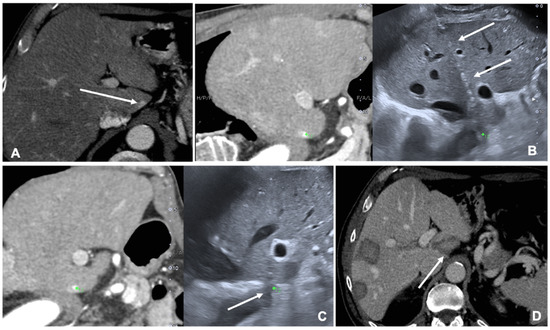

Figure 3. Case of a patient with left kidney clear cell renal cancer treated with microwave ablation (MWA). (A) Axial view during delayed excretory phase of the preoperative contrast enhanced Computed Tomography (CECT) showing a 25 mm intrarenal lesion (white arrows); (B) Fusion imaging (FI) of the same CT (left side) and intraoperative ultrasound (right side). MWA needle is marked by two solid arrows on the right. (C) FI during MWA of the lesion. Arrows point out the area of gas formation at the tip of the ablation needle. (D) An axial view of the control CT at the end of the procedure. Arrows point out the resulting completely ablated area of the kidney lesion.

FI is used to co-register previous CT or CBCT and real-time US to perform tumor ablations. Assisted CBCT and US FI are effective, safe and feasible in TA, but only a few papers investigated the advantages and limitations of these techniques [35,36,37]. A case of a patient with renal tumor treated with the guidance of FI is shown in Figure 3.